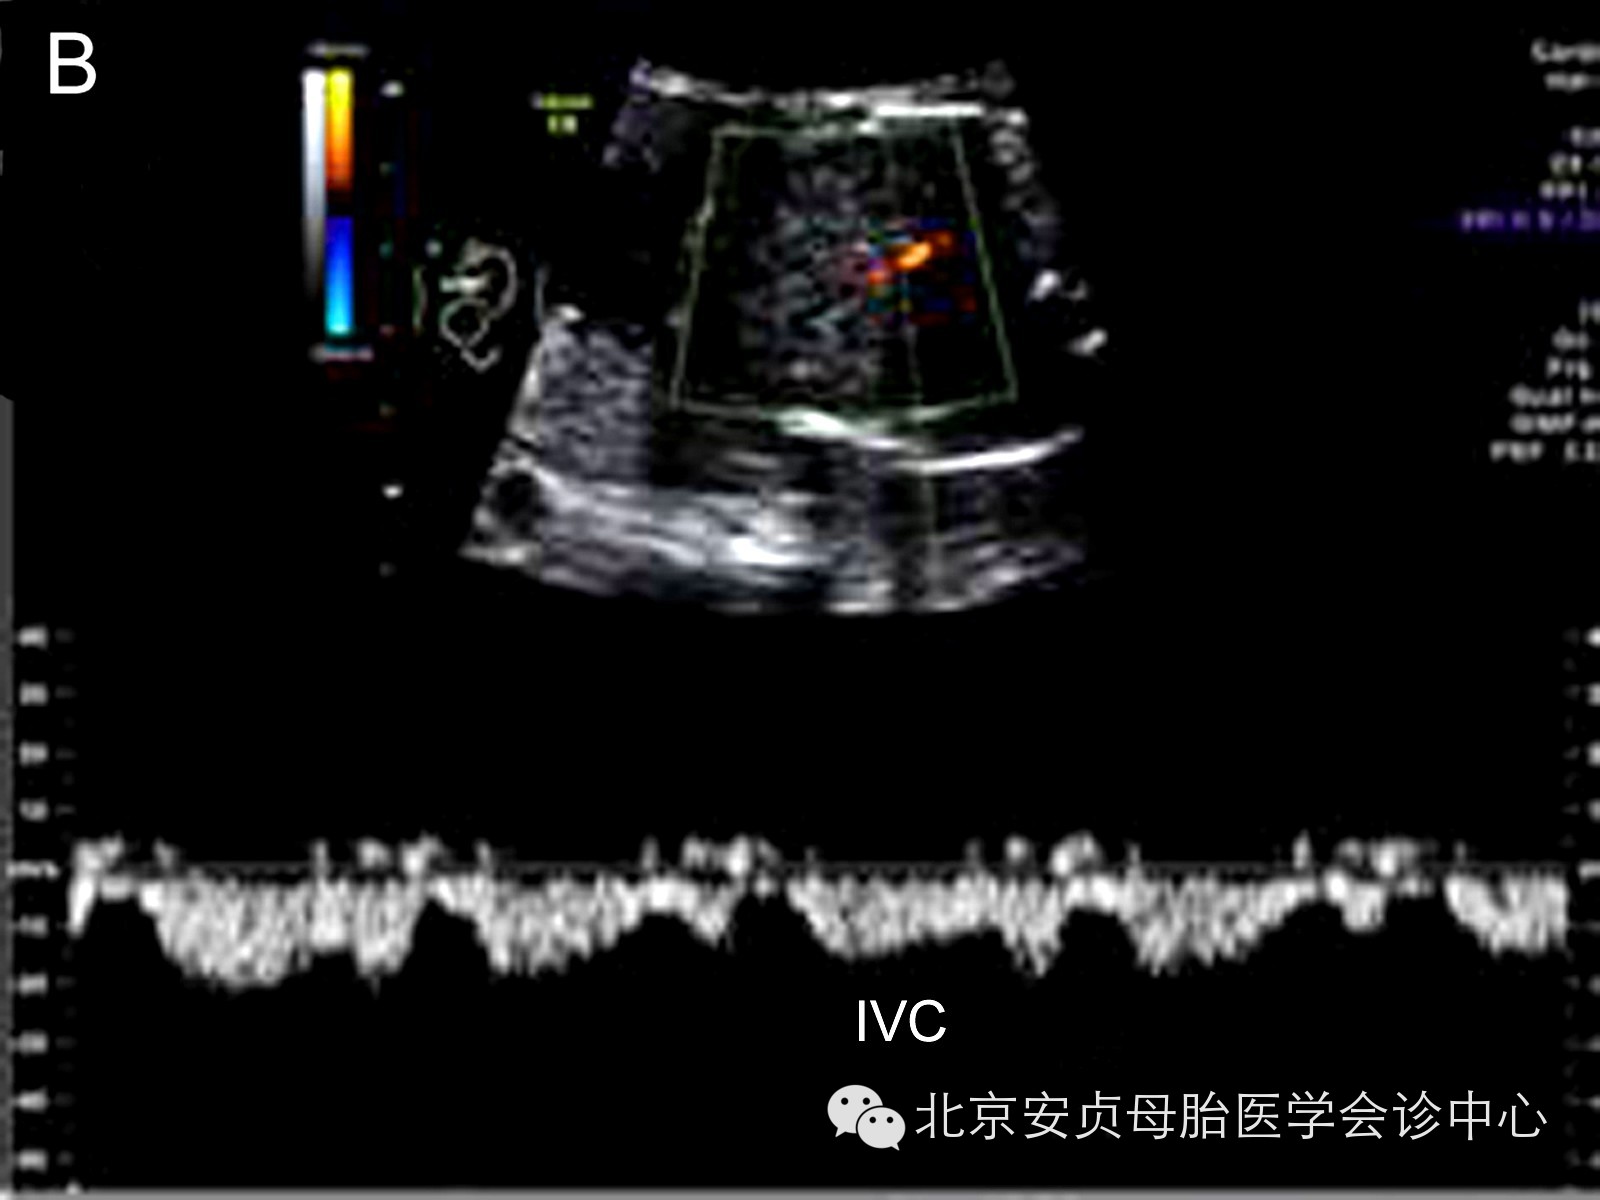

胎儿静脉血流能够客观、非特异性的用于评价心脏功能。对静脉系统频谱波形的分析主要包括:近心水平的静脉导管、下腔静脉、肝静脉、肺静脉;远心水平的腹内段脐静脉。与心房紧密相关的近心端静脉血流频谱正常均表现为多相血流波形。远心端脐静脉表现为无波动性的、低阻力连续静脉频谱波形。当上述静脉系统波形异常时,表明胎儿心脏舒张或收缩功能异常、心脏后负荷增加。

胎儿心功能不全除包括心室收缩或舒张功能减低,以下征象的出现也表明胎儿心力衰竭:心脏扩大、房室瓣反流、静脉血流频谱异常、心脏输出量重新分配(大脑中动脉舒张期血流速度增快和搏动指数减低、脐动脉舒张期血流消失或呈反向波)、胎儿水肿,如病例4,胎儿收缩功能常规测量值方面显示正常,但综合和表现提示胎儿右心功能减低。